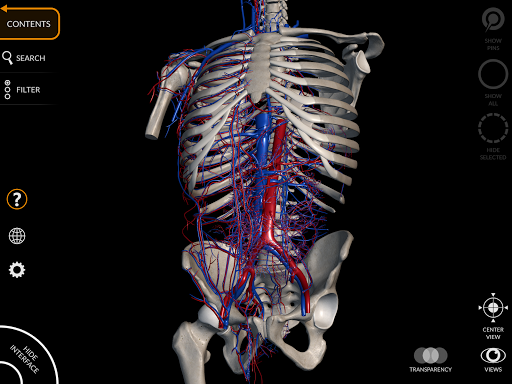

"Anatomy 3D Atlas" cho phép bạn nghiên cứu giải phẫu người theo cách dễ dàng và tương tác.

Thông qua giao diện đơn giản và trực quan, bạn có thể quan sát mọi cấu trúc giải phẫu từ mọi góc độ.

Các mô hình giải phẫu 3D đặc biệt chi tiết và có kết cấu lên đến độ phân giải 4k.

Việc phân chia theo vùng và chế độ xem được xác định trước giúp quan sát và nghiên cứu các bộ phận hoặc nhóm hệ thống riêng lẻ và mối quan hệ giữa các cơ quan khác nhau.

• Hệ thống tim mạch

• Xoay và phóng to từng mô hình trong không gian 3D

• Tùy chọn ẩn hoặc cô lập một hoặc nhiều mô hình đã chọn

• Bộ lọc để ẩn hoặc hiển thị từng hệ thống

• Chức năng trong suốt